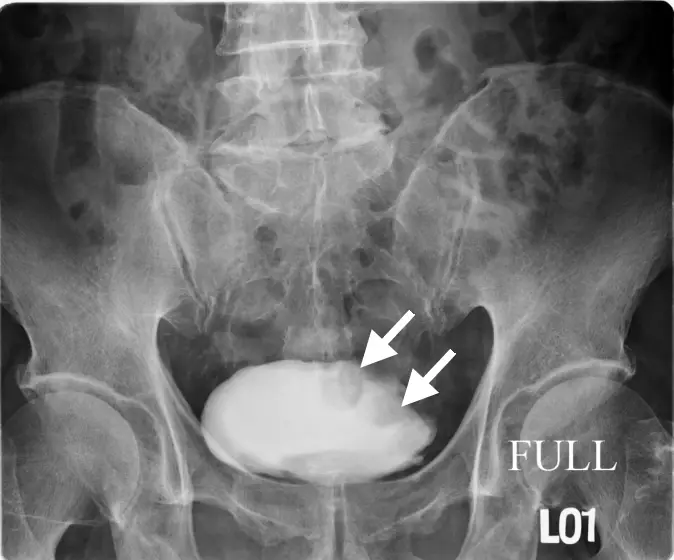

46 歲林先生因排解血尿而到醫院檢查,他並沒有其他不舒適症狀。醫師為他做 IVU 檢查顯示膀胱異常,又進一步做 CT 檢查,病變如圖示。林先生最可能患了什麼病? 圖片 圖片 圖片

圖三(CT 軸位切面,下方切面):另一層面的 CT 橫斷面,白色箭頭指向膀胱內的腫塊,腫塊形態不規則,呈乳頭狀或結節狀突入膀胱腔,膀胱壁局部增厚,整體影像特徵高度符合膀胱移形上皮癌(urothelial carcinoma/transiti